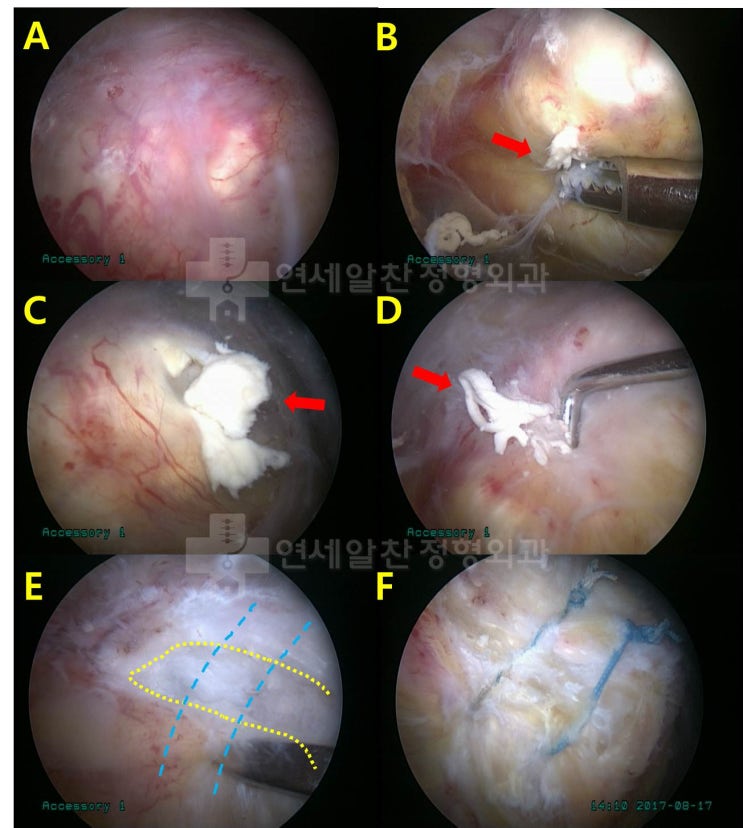

거대한 석회성 건염에서 관절경을 통한 석회 제거술 및 극상근 봉합술(side to side)

43에 여자 환자로 우측 어깨의 극심한 통증을 주소로 내원하였다. 환자는 내원 일주일 전부터 극심한 통증...

석회성 건염에서 관절경하 석회 제거술의 결과

61세 여자 환자로 좌측 어깨의 극심한 통증을 주소로 내원하였다. 환자는 타병원에서 석회성 건염을 진단 ...